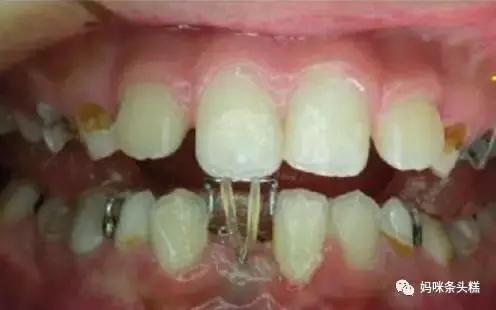

拔除后除了提供恒牙正常生长的间隙,还会需要根据牙齿埋伏的深浅程度决定是否需要进行恒牙牵引,帮助萌出。

恒牙的阻生看则是影响美观,牙齿缺失,但实际真实情况远不止于此,阻生牙牙冠周围的牙龈常常会发炎,疼痛,严重时脸颊可以肿胀,张口困难,甚至全身发热,颌下淋巴结肿大。

阻生牙常常还会引起邻牙龋坏,松动,牙槽骨吸收等症状,妈妈们有发现宝宝恒牙萌出不正常的情况,需要及时带宝宝前往牙科检查并尽早介入治疗。